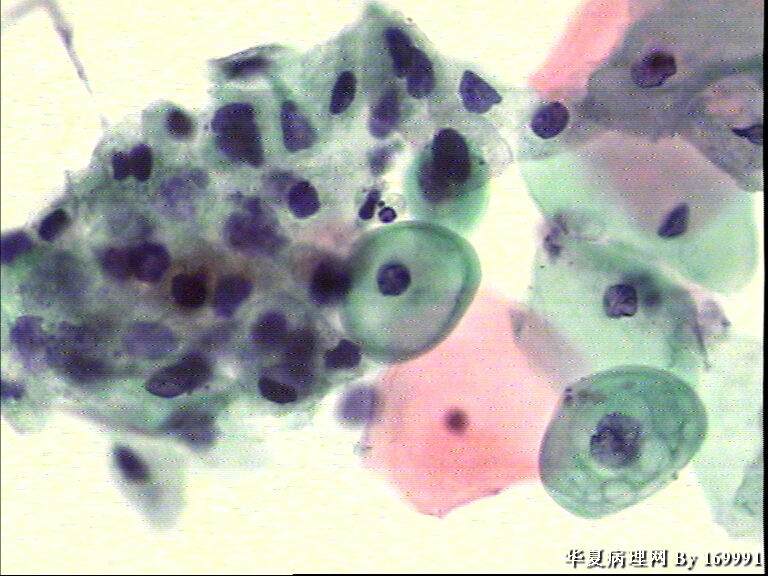

宫颈液基,患者,23岁,宫颈中糜

图1